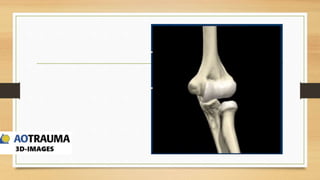

ANATOMIA

QUIRURGICA

• CAMBIO DE FORMA EN EL

HUMERO A MEDIDA QUE SE

HACE MAS DISTAL